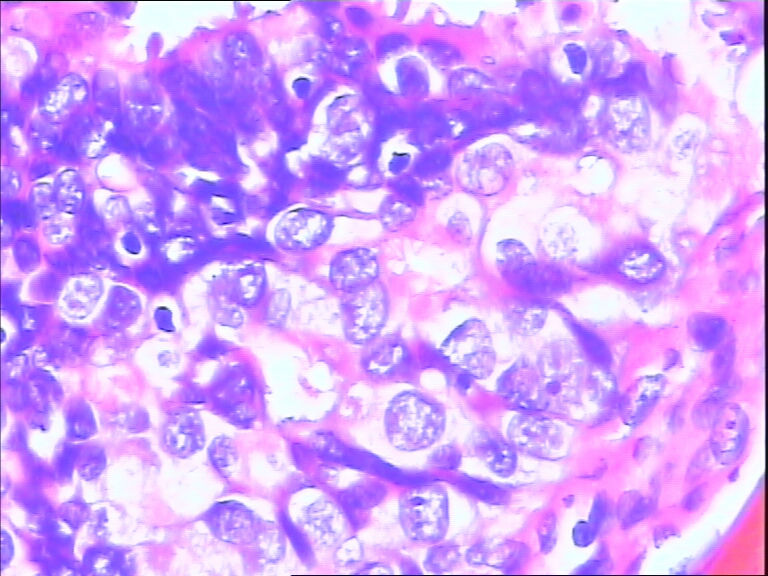

女,43y

左输卵管积液

输卵管长4.5cm;直径:0.8cm

输卵管增生性上皮病变。

慢性炎伴上皮增生

良性,炎症改变

考虑炎症